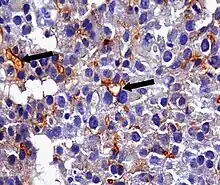

Immunohistochemistry using antibodies against CEA in a hepatocellular carcinoma, showing the typical canalicular pattern.[18]

An anti-CEA antibody is an antibody against CEA. Such antibodies to CEA are commonly used in immunohistochemistry to identify cells expressing the glycoprotein in tissue samples. In adults, CEA is primarily expressed in cells of tumors (some malignant, some benign) [19] but they are particularly associated with the adenocarcinomas, such as those arising in the colon, lung, breast, stomach, or pancreas. It can therefore be used to distinguish between these and other similar cancers. For example, it can help to distinguish between adenocarcinoma of the lung and mesothelioma, a different type of lung cancer which is not normally CEA positive. Because even monoclonal antibodies to CEA tend to have some degree of cross-reactivity, occasionally giving false positive results, it is commonly employed in combination with other immunohistochemistry tests, such as those for BerEp4, WT1, and calretinin.[20] For cancers that highly express CEA, targeting CEA through radioimmunotherapy is one of the therapy approaches.[21] Engineered antibodies such as single-chain Fv antibodies (sFvs) or bispecific antibodies have been used for targeting and therapy of CEA expressing tumors both in vitro and in vivo with promising results [22][23] Regions of high CEA levels in the body can be detected with the monoclonal antibody arcitumomab.[24]